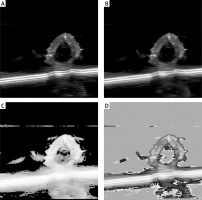

In this study, the quality of multimodal images (ultrasound and CTA) of atherosclerosis was found to directly impact the performance of the DL model. Therefore, preprocessing techniques including denoising, contrast enhancement, and image normalization were employed. Gaussian filtering reduced unnecessary noise, while histogram equalization improved the visibility of plaque lesions. To ensure consistency among the multimodal images used as model inputs, normalization was applied so that the input features shared a unified distribution range. Figure 1 compares raw and preprocessed images, clearly illustrating the improved detail in lesion areas. All images were annotated by experienced radiologists, focusing on plaque shape, location, and type. The annotation data were cross-validated to ensure consistent boundaries and accurate feature delineation. Table I summarizes the sample distribution across the training, validation, and test sets, thereby providing balanced support for subsequent model development. In addition, Table II systematically compares the differences between the model developed in this study and current mainstream methods in terms of data modalities, multi-task design, and performance metrics, further highlighting the innovative aspects of this model.

Figure 1

Comparison of image preprocessing effects. A – Original image: lesion areas appear blurred and noisy. B – After denoising: noise is reduced and vessel boundaries are clear (Gaussian blur denoised). C – After contrast enhancement: plaque regions are significantly enhanced (histogram equalized). D – After normalization: image details are uniformly presented